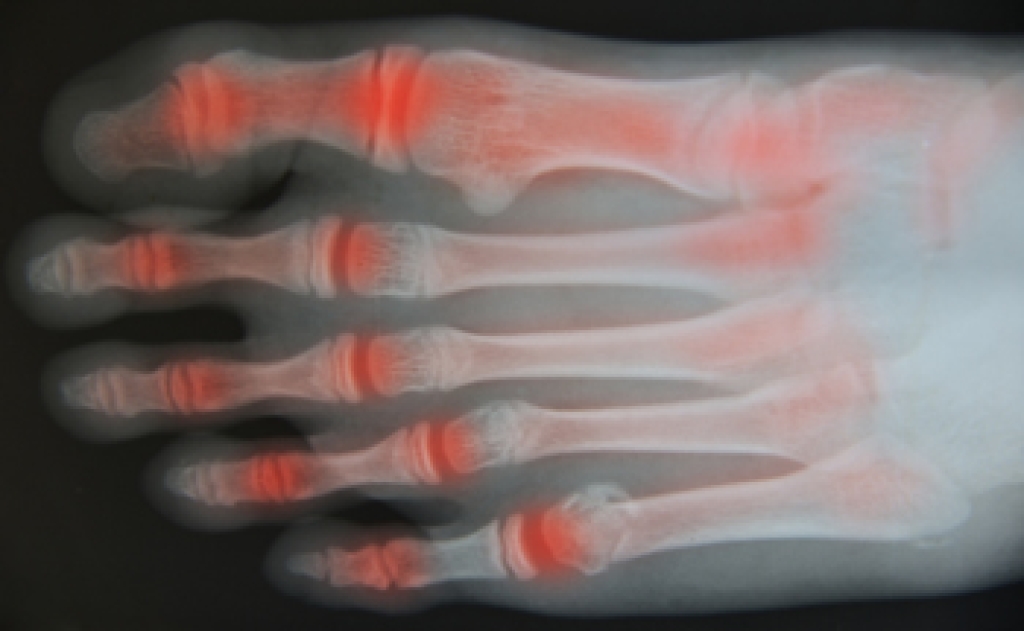

Toe Arthritis

Arthritic pain and stiffness in the toes often develop gradually and can make walking, standing, or wearing shoes uncomfortable. Degenerative joint changes are a common cause, especially with aging, past injuries, repetitive stress, or long-standing foot mechanics that overload small joints. Inflammatory conditions and autoimmune disease may also affect the toe joints. Common signs include aching or burning discomfort, swelling, reduced range of motion, and difficulty pushing off while walking. Some people notice joint enlargement, altered toe position, or increased pain with cold weather or activity. Care focuses on reducing stress through footwear changes, activity modification, and custom orthotics to improve alignment. Anti-inflammatory strategies, targeted exercises, and injections may help manage symptoms. In advanced cases, surgical options can restore function or relieve pain. Early evaluation often prevents progression and protects mobility. If you feel pain or stiffness in your toes, it is suggested that you see a podiatrist for a proper evaluation and treatment options.

Arthritis is a joint disorder that involves the inflammation of different joints in your body, such as those in your feet. Arthritis is often caused by a degenerative joint disease and causes mild to severe pain in all affected areas. In addition to this, swelling and stiffness in the affected joints can also be a common symptom of arthritis.